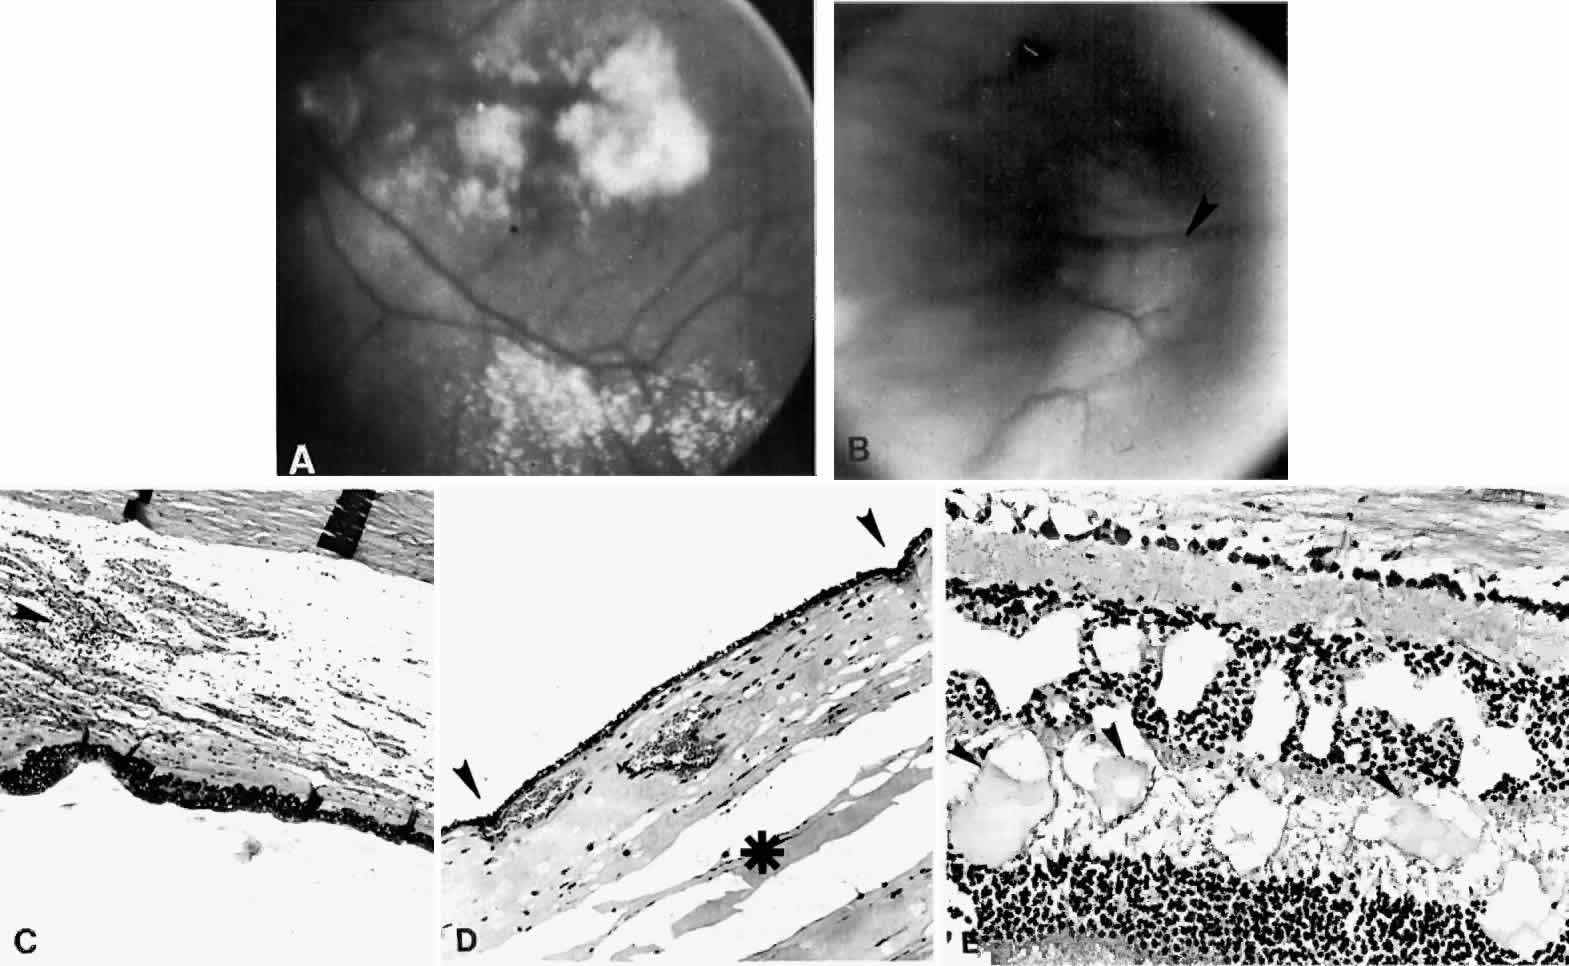

Various surgical procedures may be complicated by a ciliochoroidal effusion during or after the procedure. An expulsive effusion can mimic an expulsive hemorrhage during cataract extraction33–36 or glaucoma surgery, especially in patients with prominent preoperative episcleral vessels, as in Sturge-Weber syndrome.37 Varying degrees of postoperative suprachoroidal edema may develop after cataract extraction (Figs. 7 and 8),1,9,32–34,38–46 iridectomy (Fig. 9), filtering procedures (Fig. 10),1,9,32,37,47–49 retinal detachment surgery (Fig. 11),50–54 panretinal photocoagulation,55,56,56a or cryotherapy. A postoperative ciliochoroidal effusion can occur weeks, months, or even years after surgery.40,57 Between 1 and 18 months after filtration surgery, hypotony and ciliochoroidal detachment developed in four patients when timolol or acetazolamide therapy was instituted.57

Fig. 7. Large lobule of a ciliochoroidal effusion that occurred after cataract extraction.

Fig. 8. This choroidal and ciliary body detachment, which occurred after intracapsular cataract extraction, was mistaken for a malignant melanoma.39 A. Iris incarceration in the wound (arrow) and extensive ciliary body effusion consisting of a dense, proteinaceous material (asterisk) (H & E, × 115). B. Effusion of the choroid near the ora serrata by a moderately dense, proteinaceous material without inflammatory cells. Note folds of choroid (arrowheads) (H & E, × 115).

Fig. 9. A. This serosanguineous ciliochoroidal effusion (arrow), which occurred after iridectomy for an iris melanoma in a 68-year-old man, was mistaken for a choroidal melanoma (H & E, × 25). B. Site of the limbal wound (arrowhead) with incarceration of the iris base and residual melanoma in the iris, anterior aspect of the ciliary body, and trabecular meshwork (H & E, × 60).

Fig. 10. A. This extensive ciliochoroidal effusion (asterisk), which occurred 4 years after iridencleisis in a 70-year-old man,39 was mistaken for a malignant melanoma. The iris (arrow) is incarcerated in the limbal wound, and a flat, edematous infiltration bleb (arrowheads) is present (H & E, × 25). B. Area of the ora serrata shows a ciliochoroidal effusion with proteinaceous material separating the tangentially oriented collagen fibers (arrowheads) that connect the choroid and ciliary body to the sclera (H & E, × 115).

Fig. 11. A ciliochoroidal effusion that developed after retinal detachment surgery. (Courtesy of Retina Service, Wills Eye Hospital, Philadelphia.)